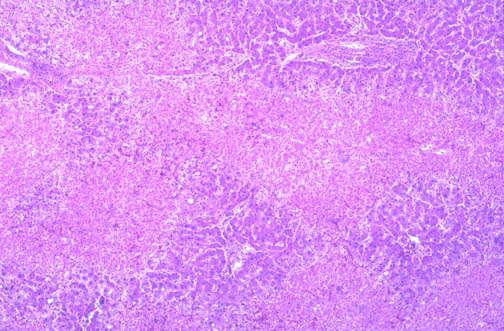

Image 7.1

This is a low power microscopic view (H&E stain) of the liver.